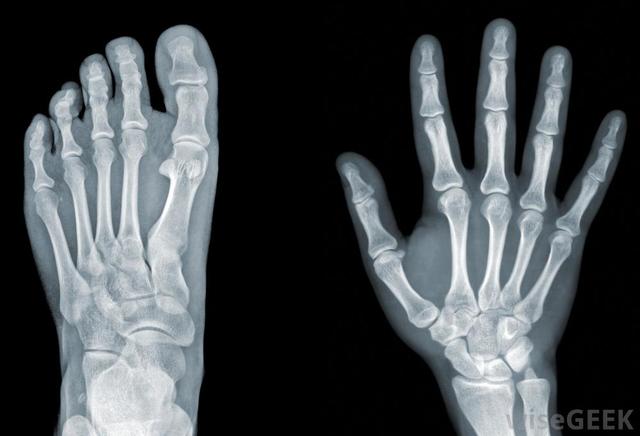

Wilhelm Roentgen accidentally discovered X-rays in radiation experiments with cathode rays ( electrons). He realizes that the rays can penetrate opaque black paper wrapped around a cathode ray tube , causing a form that shines with fluorescence. Their discovery revolutionized physics and medicine, which earned him the first Nobel Prize in Physics in 1901 .